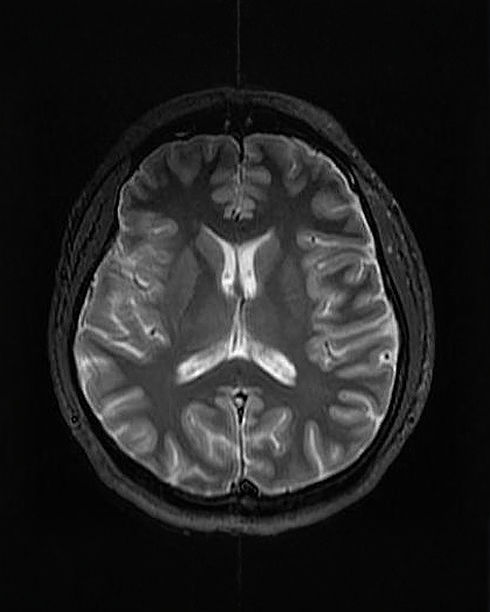

The use of imaging techniques such as CT or MRI scanning, and neurophysiological tests such as electroencephalography (EEG), electromyography (EMG) or Nerve Conduction Studies may be a necessary part of the diagnostic process in a range of clinical presentations.